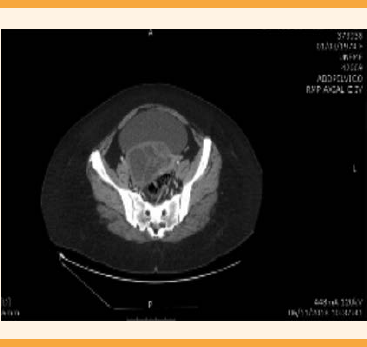

En la exploración física se encontró el abdomen blando, depresible, útero no delimitado, con anexo derecho aumentado de tamaño. En el ultrasonido pélvico se observó una tumoración en el anexo derecho, multiloculada, de aspecto complejo (Figura 1). La tomografía axial computada abdominopélvica reportó una lesión compleja, multiloculada, de paredes y septos gruesos, desplazamiento del útero hacia la izquierda, de aproximadamente 9.3 x 7.2 x 10.1 cm (Figuras 2 y 3). Se sospechó una tumoración de anexo, sobre todo dependiente del ovario. Por eso se solicitó la cuantificación del marcador tumoral Ca 125 que se reportó con valores dentro de límites normales. La citología cervicovaginal fue negativa para displasia.

Figura 3 TAC, corte transversal donde se observa una tumoración pélvica, sin componente sólido, de apariencia multiquística.